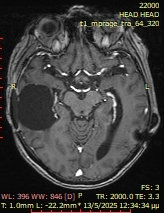

Το δόγμα της σύγχρονης χειρουργικής όγκων απεικονίζεται στις μαγνητικές αυτές. Στόχος μας είναι η μέγιστη δυνατή ασφαλής αφαίρεση του όγκου. Δεν πρέπει να στοχεύουμε στην εξαίρεση όχι μόνο του όγκου, όπως φαίνεται στην μαγνητική αλλά και στην αφαίρεση και της διηθητικής ζώνης και της υγιούς περιβάλλουσας περιοχής αν αυτή δεν έχει λειτουργίες. Η εικόνα 1α είναι προεγχειρητική, εδώ έχει σχεδιασθεί το εύρος της στοχευμένης εξαίρεσης. Η εικόνα 1β δείχνει το μετεγχειρητικό αποτέλεσμα μιας υπερολικής εξαίρεσης. Πρόκειται για την πρώτη ασθενή που χειρουργήθηκε στην Ελλάδα από τον Καθ. Γούσια τον Οκτώβριο του 2023, η οποία διαγνώσθηκε με την πιο επιθετική μορφή του γλοιοβλαστώματος, το λεγόμενο γλοιοσάρκωμα, η οποία 20 μήνες μετά την χειρουργική επέμβαση παραμένει χωρίς ένδειξη όγκου στην μαγνητική και το πιο σημαντικό χωρίς νευρολογικά ελλείμματα.